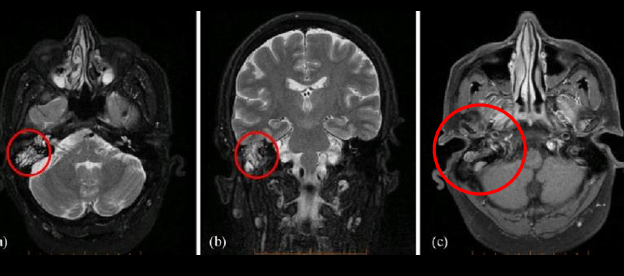

RM en otitis media

T1 - masa hipointensa en odio intenso

T2 - masa hiperintensa en odio y mastoides